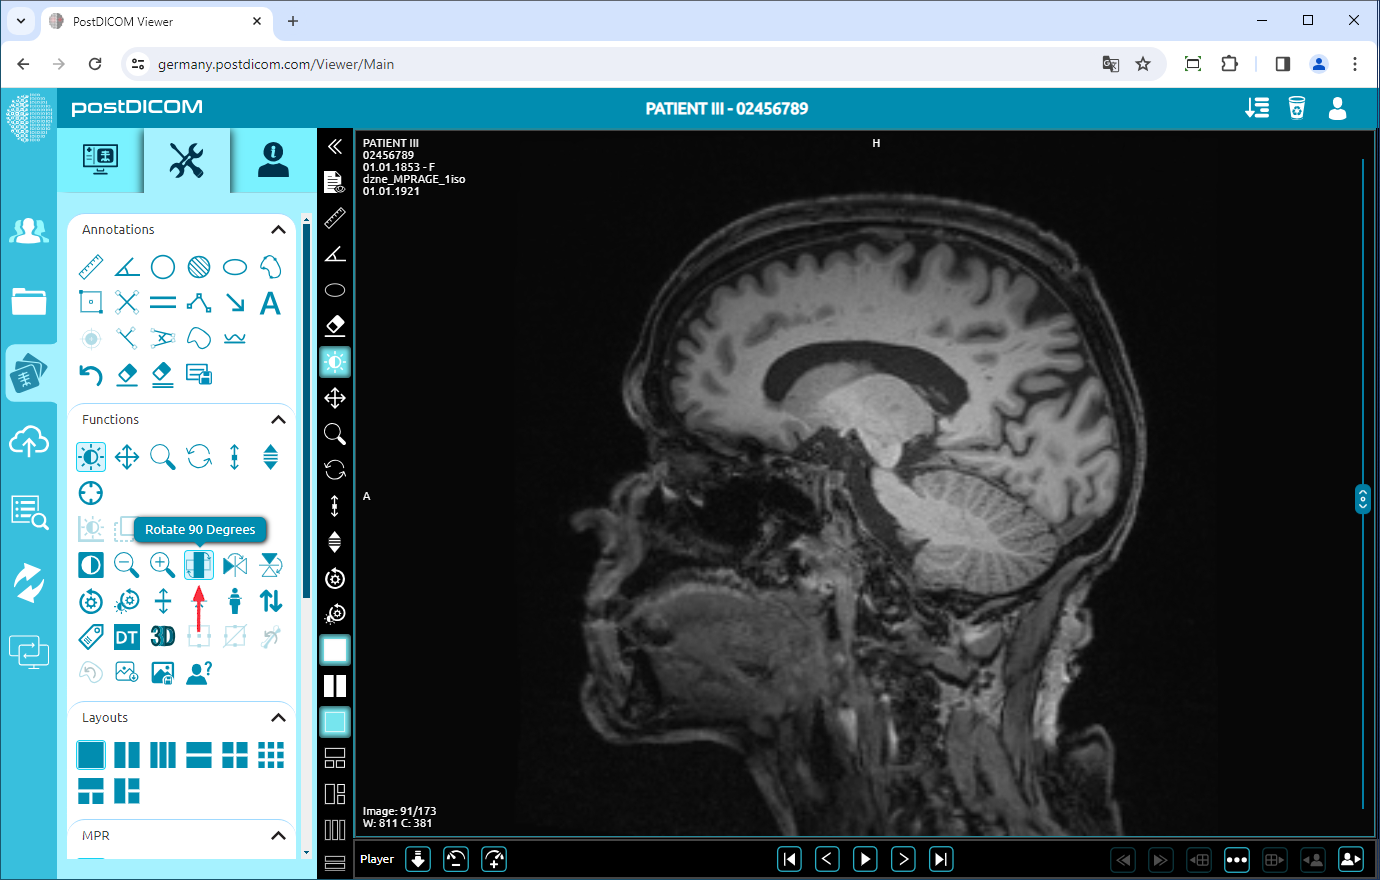

Rotate

Click on the “Rotate 90 Degrees” icon on the left side of the page.

If you click once, the image will rotate 90 degrees to the right. You can click twice to rotate the image 180 degrees, three times click to rotate it 270 degrees or four times click to rotate it 360 degrees (return to the original plane). The image rotated 90 degrees is shown below.